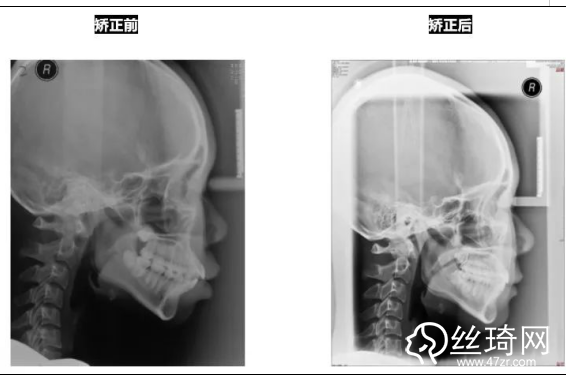

* 影像學(xué)檢查分析(以及調(diào)節(jié)前后影像對比):

頭顱側(cè)位片:

前后頭影測量結(jié)果對比: